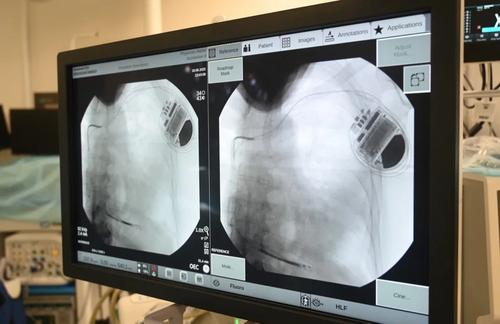

Подкожный кардиовертер-дефибриллятор устанавливается под широчайшую мышцу спины в подмышечной области, а электрод проводится подкожно на переднюю грудную стенку и устанавливается в проекции сердца. Прибор контролирует активность сердца и, когда оно останавливается, начинает биться неправильно, слишком медленно или слишком быстро, благодаря специальным алгоритмам аппарат посылает электрические импульсы, позволяющие восстановить нормальный сердечный ритм.

Впервые подкожную систему кардиовертера-дефибриллятора установили пациенту медики больницы им. В.В. Вересаева год назад. Сегодня такие вмешательства проводят в операционных ГКБ им. С.С. Юдина, ГКБ им. В.В. Вересаева и ГКБ им. И.В. Давыдовского.